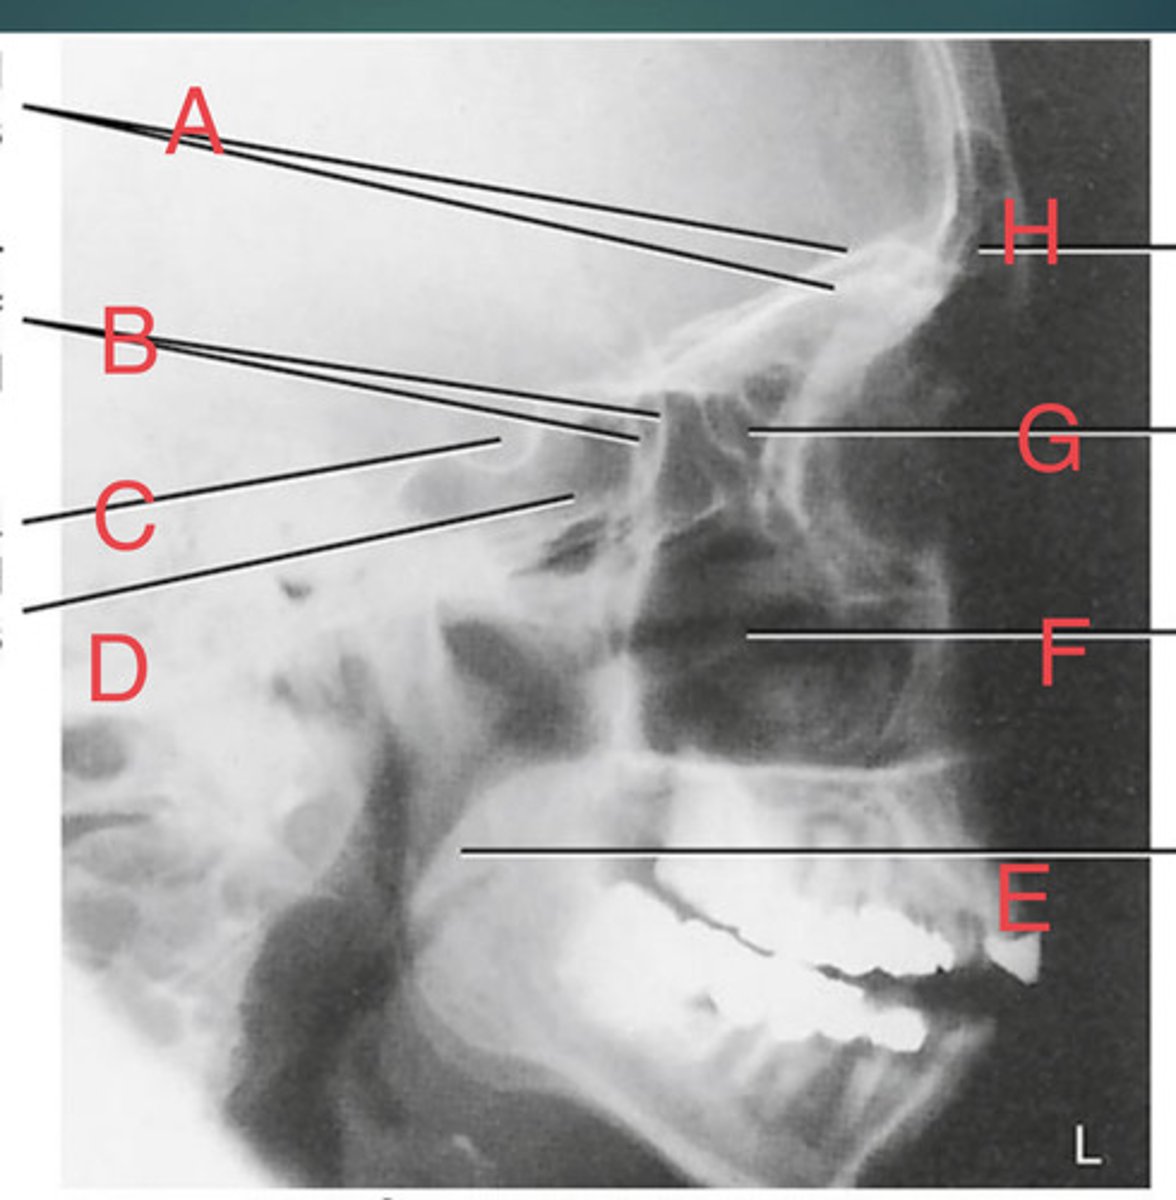

Lateral sinus

What position?

L. Orbital roofs

A.

L. Greater wings of sphenoid

B.

sella turcica of sphenoid

C.

L. Sphenoid sinus

D.

L. Rami of mandible

E.

L. Maxillary sinuses

F.

L. Ethmoid sinuses

G.

L. Frontal sinuses of frontal bone

H.